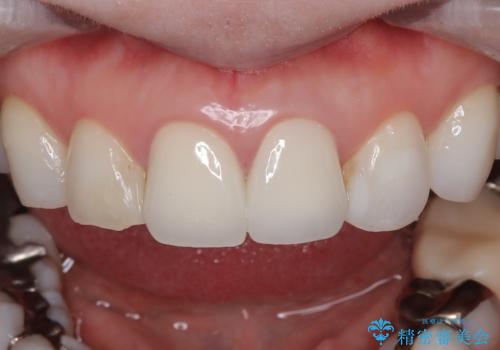

- [前歯の色が気になる」を主訴に来院された患者様です。歯の形を整えた後オールセラミッククラウンで治療を行いました。

- 308,000円(オールセラミッククラウンスペシャル154,000円×2)費用は治療当時の料金となります

歯の形を整えた後、色が透けないよう処置をしてオールセラミッククラウンで治療を行いました。